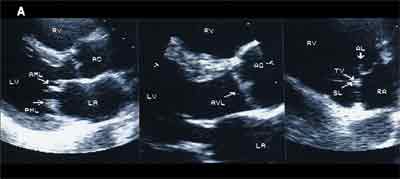

An echocardiographic study showed abnormally thickened and rigid mitral, aortic, and deformed tricuspid leaflets (A). Color flow Doppler images showed abnormal regurgitation at all 3 valves without stenosis (B). Peak right ventricular pressure was 26 mm Hg. Left ventricular function was normal (estimated ejection fraction of 60% to 65%). Because no previous echocardiogram-obtained before the patient started taking the drugs-was available, images of normal cardiac valves are shown for comparison (C).